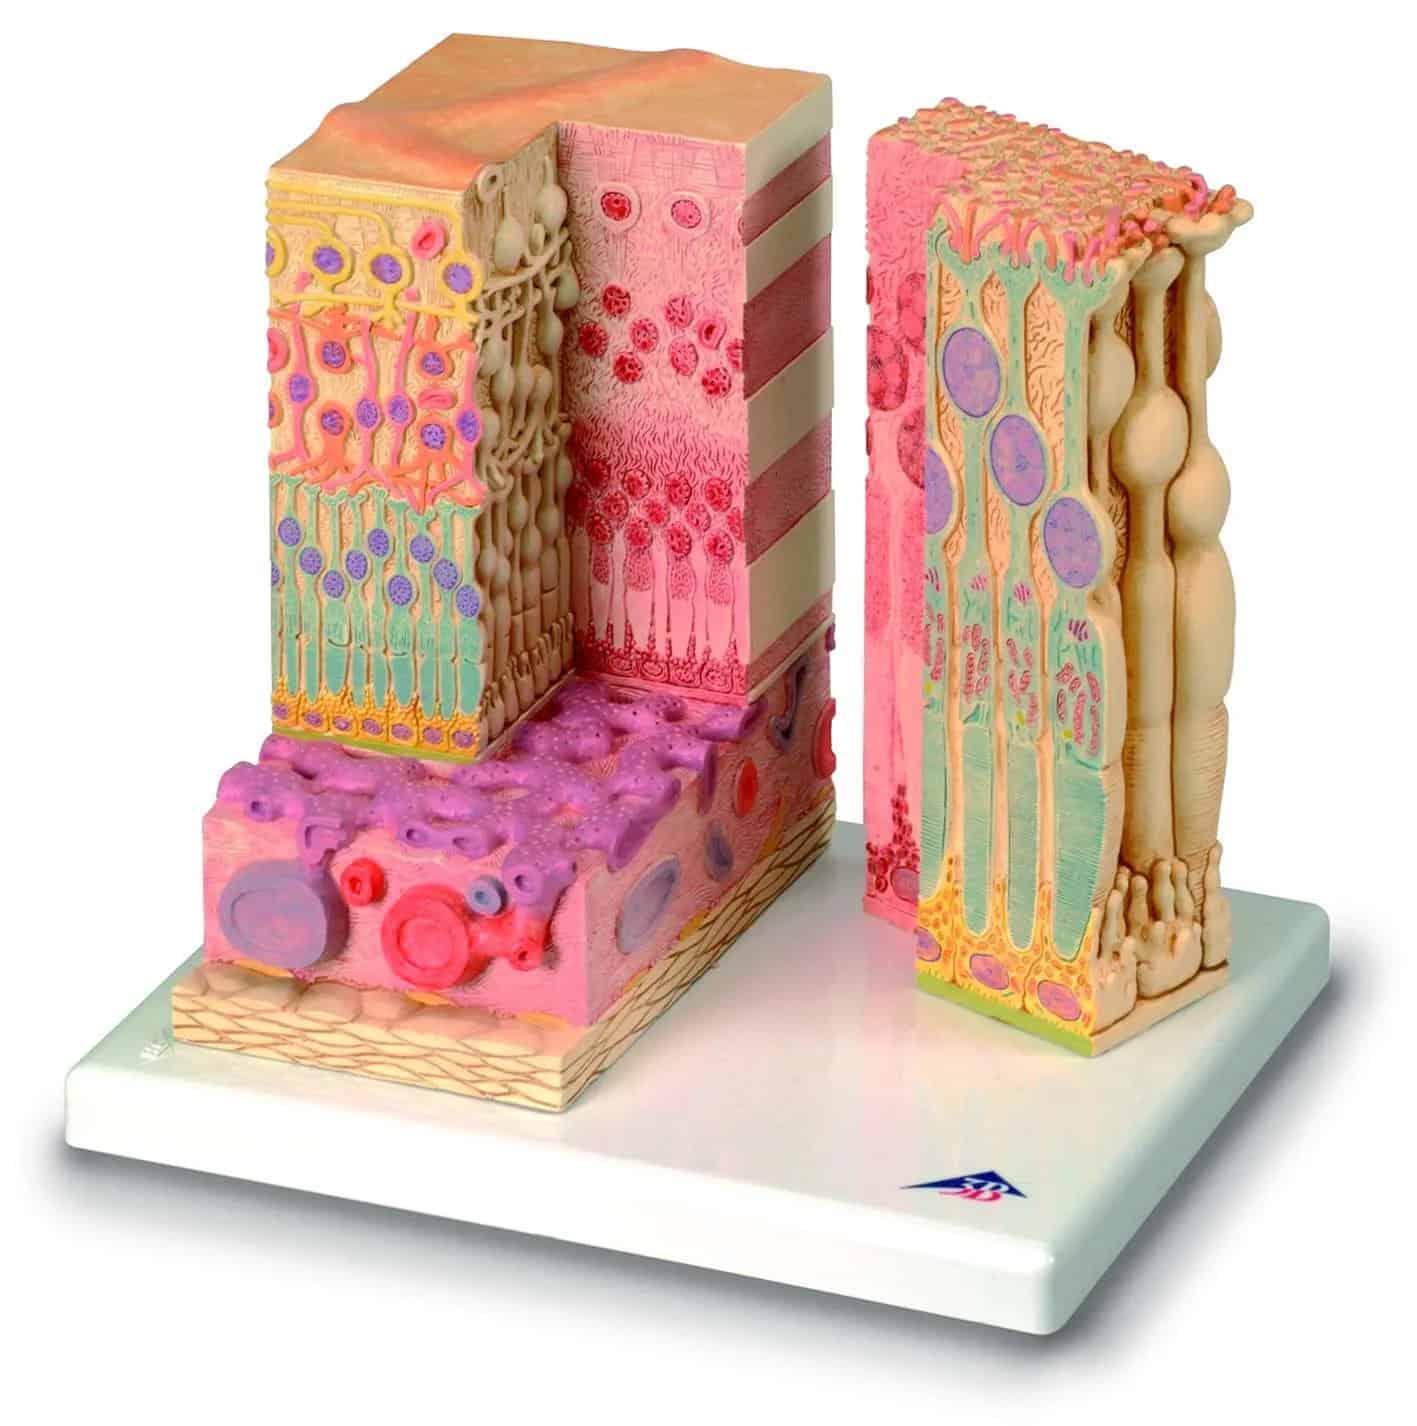

1000200

Torso tweeslachtig met open rug 28-delig